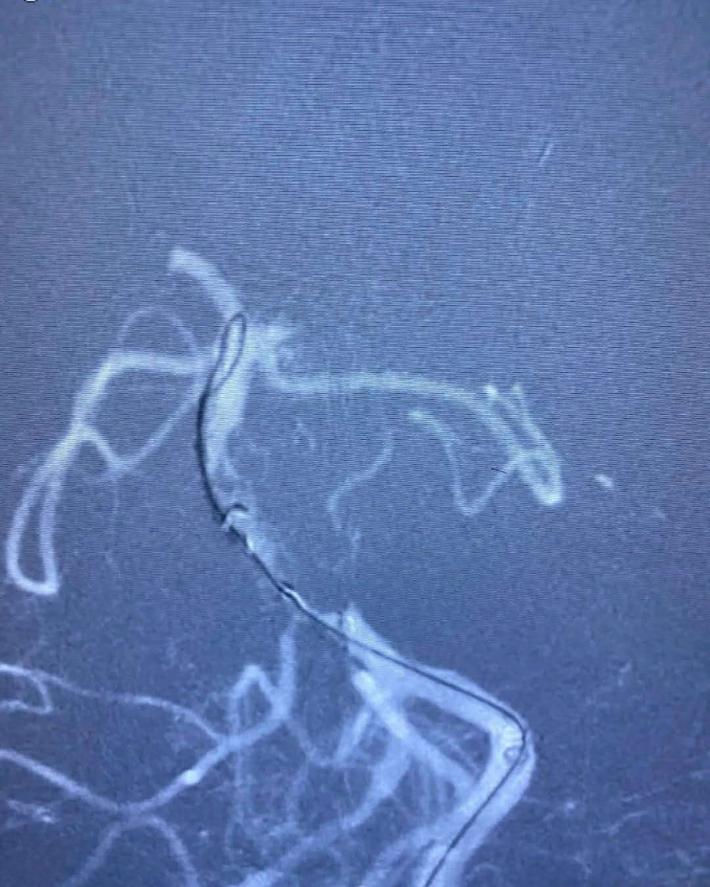

Solitaire AB 4mmx20mm成功挂住Enterprise 2。

尝试回收支架至5F Navien,牵扯力量比较大,提心吊胆。

经反复收拉尝试,最终取出Enterprise 2支架。

Enterprise 2支架在血管内两端严重变形,反折的Mark恰好被Solitaire AB支架咬合取出。

造影未见出血,血流良好,原狭窄在第一次支架时球囊扩张,现在狭窄已缓解。狭窄远端血管内膜稍不光滑。观察30min,血流稳定,为避免再放支架血栓,同时本次预后尚未知,暂不植入第二枚支撑支架,予以替罗非班注射液应用。